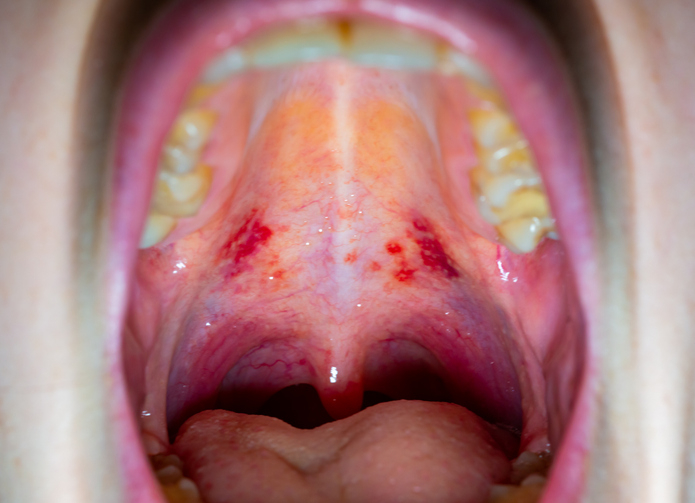

두경부암의 대표적인 원인은 '흡연'과 '음주'다. 특히 구강·인두·후두는 흡연·음주의 양·기간에 따라 암 발병률이 증가한다는 점이 여러 연구에서 확인됐다. 최근에는 성관계를 통해 전파되는 인유두종바이러스(HPV)가 추가적인 주요 원인으로 밝혀졌다. 특히 편도·혀뿌리·연구개(물렁한 입천장) 등에 발생하는 인두암에서 HPV가 검출될 비율이 50~80% 나타나며, 이는 HPV와 구인두암의 높은 상관관계를 보여준다.

두경부암은 치료 예후가 좋지 않아 조기 진단이 중요하다. 암이 이미 진행된 경우에는 치료 범위가 넓어져 △먹기 △말하기 △숨쉬기 등 필수 기능에서 장애를 보인다. 근치적 치료를 하더라도 재발 확률이 높고 5년 이상 생존율이 매우 낮다. 조기 진단을 위해서는 의심 증상이 있을 때 병원을 찾아 진료받아보는 게 좋다. 두경부암의 주요 증상으로는 입안 궤양이 지속되거나, 입안에서 덩이가 만져지거나, 통증, 구취, 음성 변화 등 있다. 병원에서는 두경부암이 의심되면, 후두경으로 비강부터 후두까지 전반적으로 관찰하고 필요시 조직검사나 세침 검사를 해서 확진한다.